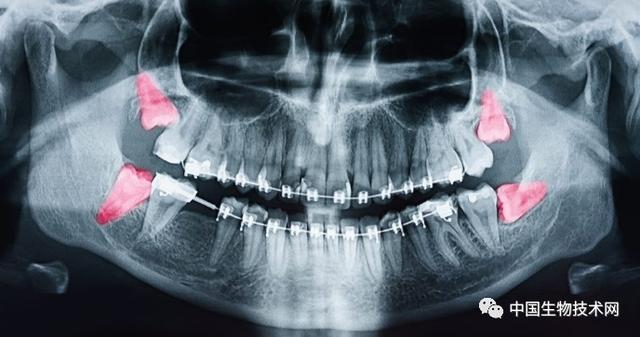

在人类近亲中,只有黑猩猩像我们一样会延长在关键发育期的时间。但即使是黑猩猩,也早早长齐了满口牙。而现代智人直到青春期结束才开始萌出第三磨牙,即阻生智齿(俗称智齿)。健康的智齿可以帮助咀嚼,但有问题的智齿可能会引起牙龈组织发炎和感染,最终导致冠周炎。所以,很多人不得不拔掉有问题的智齿。

早期人类的口腔空间并不像现在这样大,阻生智齿(俗称智齿)是我们人类面临的一个主要问题。但这并不能解释为什么它们在我们的生命中出现得这么晚,或者为什么后面的那些智齿似乎总在制造麻烦。